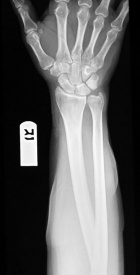

M.M. - 53 year old male with a painful right forearm mass

Zoom image: Radiological image Radiological image.

Zoom image: Cell stain Cell stain.